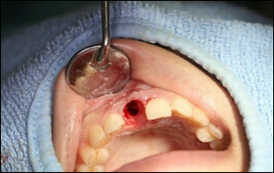

歯を抜いた写真です。

インプラントを入れる穴を開けた写真です。

写真から見てわかるように、出来るだけ歯ぐきを切らずにインプラントを入れています。

通常インプラント手術では、骨が直視できる状態の方が埋入を簡単に行えるため骨が露出するまで歯ぐきを切開します。ですが歯ぐきを一度はぐと血流が途絶え、傷の回復に時間がかかります。

上の写真のように歯ぐきをはがずにインプラントを埋入することをフラップレスといいます。

当院ではできるだけフラップレスを行っています。